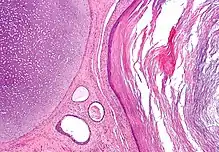

Micrograph of a teratoma, a tumour that characteristically has tissue from all three germ layers. The image shows tissue derived from the mesoderm (immature cartilage - left-upper corner of image), endoderm (gastrointestinal glands - center-bottom of image) and ectoderm (epidermis - right of image). H&E stain.